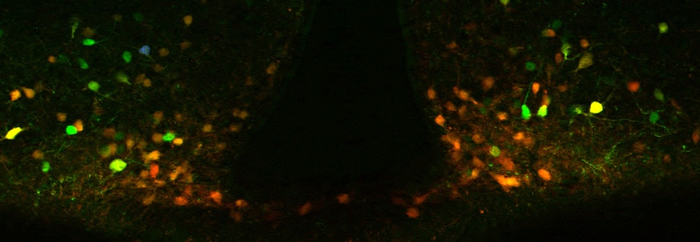

The new research focused on a class of cells in the brain called POMC neurons, which are associated with reduced appetite, lower blood glucose levels, and higher energy burning when activated. A 2019 study from Dr. Williams showed a single bout of exercise can boost the activity of POMC for up to two days.

In the latest research, the Williams lab found this neuron also plays a critical part in how celastrol impacts weight loss. Mice given the compound saw decreased activity of a protein called PERK within the region of the brain where POMC neurons reside. The lab further found that deleting PERK from these neurons can replicate much of the weight-loss effects of celastrol, and appears to do so without causing harmful side effects often associated with anti-obesity drugs.